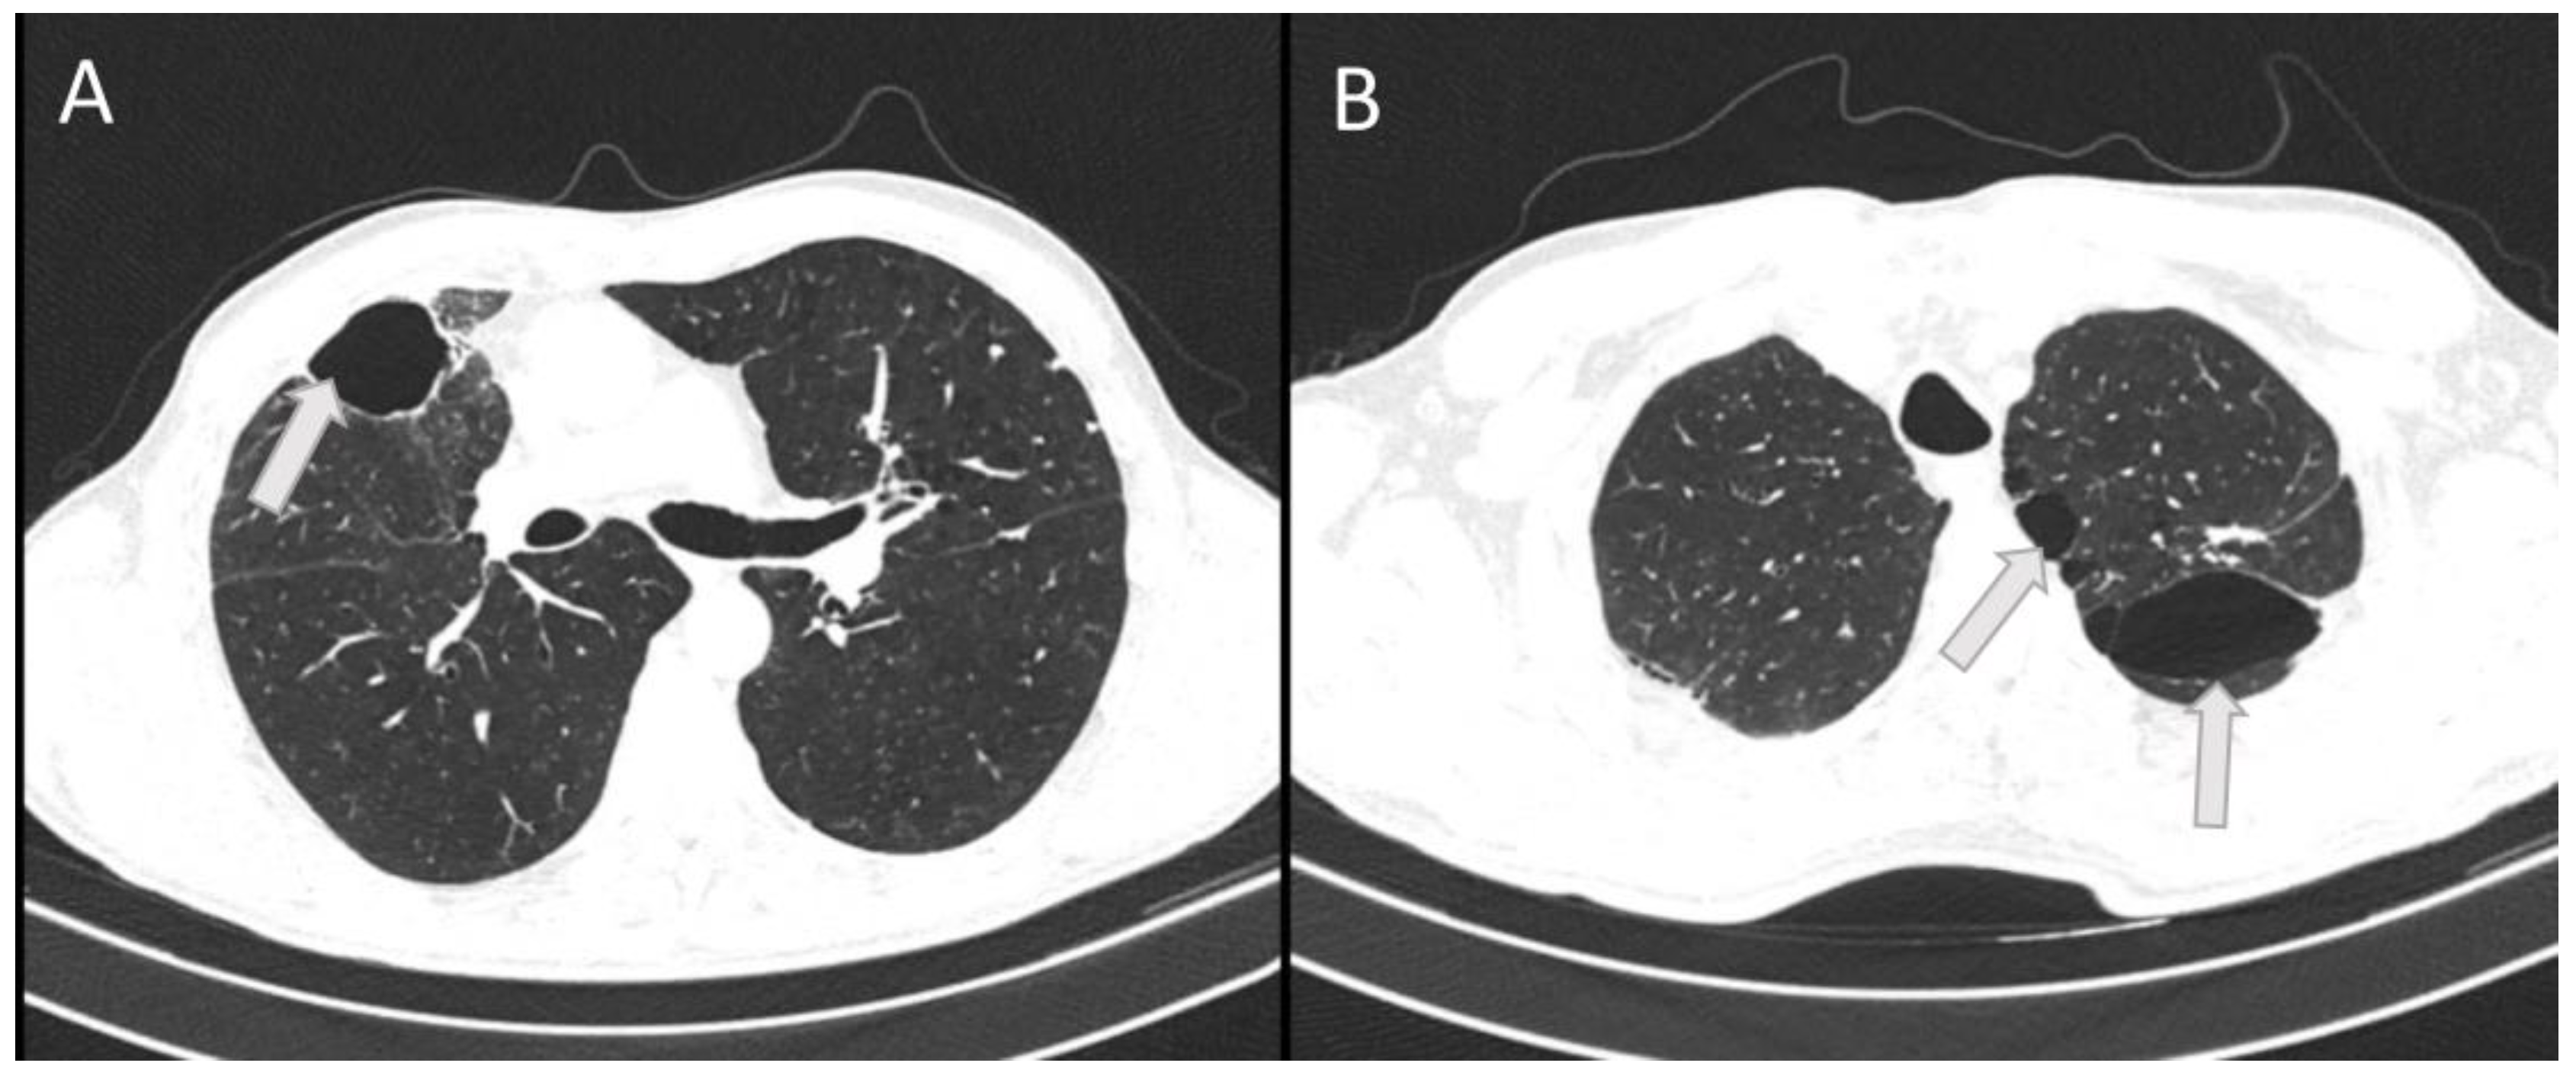

Figure 4. The horizontal CT scan section at the level of the 6th thoracic vertebra (A) and at the level of the 3rd thoracic vertebra (B) showing residual bullous changes (arrows) 6 months after severe chest injury with bilateral pneumonia in a 53–year-old patient.

On this outpatient examination, a CT scan of the lung was performed which confirmed bullous changes in the left side of the lung (Figure 4). Subjectively, he had discomfort when breathing and pain in the right chest. He complained about poor physical condition. His medical therapy prescribed by a pulmonologist was ipratropium bromide (Atrovent N, Boehringer Ingelheim Pharma GmbH & Co., Germany) 3 x 2 breaths.

High ventilation pressures can improve oxygenation but may increase the risk of barotrauma in the healthy lung. Due to lower resistance, a larger volume of inhaled gas will be directed to healthy areas of the lungs [13]. This is the reason that bullous changes after mechanical ventilation in our patient were also found in the lung areas that were less affected by trauma and inflammation.

Barotrauma can lead to the destruction of alveoli, parenchymal bleeding, and acute infiltration during the acute injury itself. After the resolution of the inflammatory reaction, due to the resulting residual fibrosis, these affected alveoli will not contribute to gas exchange. Impaired perfusion can also be expected in tissues after severe inflammation. The consequence of post-traumatic and post-inflammatory events in our patient was an increase in non-functional residual lung volume, with the development of emphysema, and decreased gas exchange function. A residual volume of 40% of the total lung volume measured in our patient is a poor prognostic sign [15].